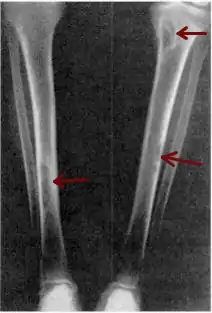

X-ray of a pair of human tibia, which run from the top right and left corner of the image into the bottom center, where they almost converge.  Small gray blemishes, identified as brown tumors, can be seen at the top and halfway down the right tibia and about three-quarters down the length of the left tibia.

Osteitis fibrosa cystica of the tibia. Arrows point to the brown tumors which are typically present in bones of people with OFC.